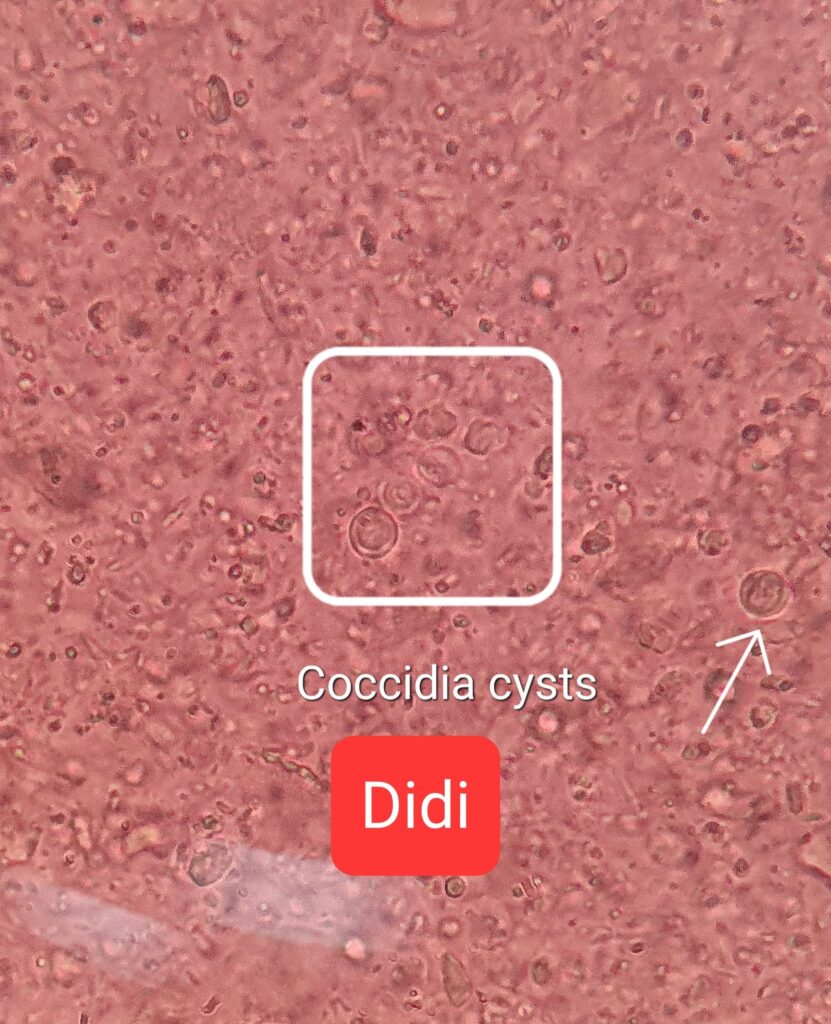

Morning: super cute. Thru out queuing for grooming. I let him cut nails and clean ears. Just now send out his poo for checking 4.75/10.

“Didi, Snap Giardia test, negative

Got coccidia cysts” – have to be on sacc le